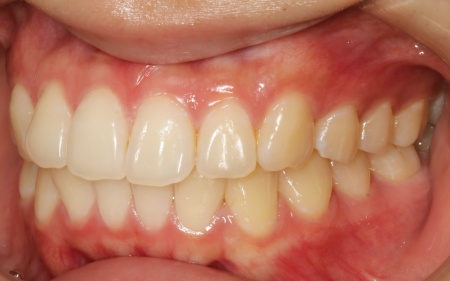

20代女性 乱れた上下の歯並びをハイブリッド矯正で改善した症例

拝見したところ、上下の歯はデコボコに生えている状態でした。

歯の移動が完了したあとは定期的に経過を確認しながら、後戻りを防ぐためのリテーナー(保定装置)を継続して使用いただき、治療を終了しました。